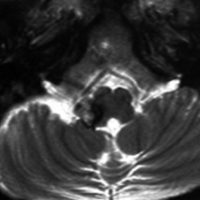

髄芽腫に対する脳脊髄照射36グレイ,8年後のMRI画像です。右前頭葉にごく小さな出血がみられます。その周囲に黒くにじむようなヘモジデリン(鉄)の沈着があります。よく見ると大脳の数カ所に同じような所見がありました。これは脳照射後の微小な静脈の閉塞に起因する血管からの微小な血液漏出 blood cell leakageです。症状を出すこともなく心配ありません。放射線治療後多発性海綿状血管腫と表現されることもあります。